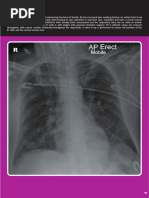

AP view

•Patient is too ill to stand or non-cooperative

•Heart at a greater distance from film, appears

enlarged

PA vs AP view

PA view AP view

Clavicle Over lung fields Above lungs apex

Scapulae Away from lung fields Over lung fields

Ribs Posterior ribs distinct Anterior ribs distinct

Heart Relatively enlarged